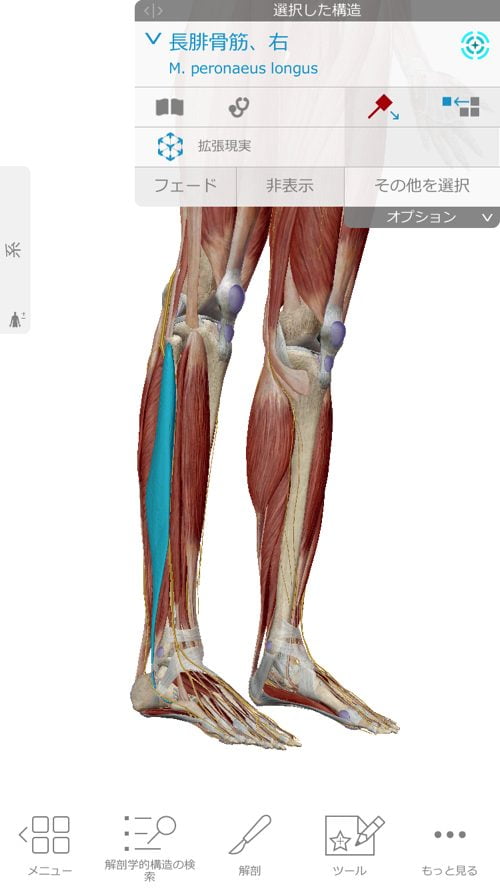

さらに膝に出来た余裕を利用してこの長腓骨筋を緩めて調整します。

今回、特にしっかりと調整したのはこの長腓骨筋です。

それは何故かというと・・

長腓骨筋は足裏からクルブシを通って膝の方へ繋がっていきます。

長腓骨筋は膝・足首・足裏・足の指に全て影響するのがお分かり頂けたと思いますが

足だけ、膝だけ・腰だけと部分部分で切り取った見方では、脚全体の硬直や捩れ、微妙なズレなどは絶対に分からないし、レントゲンやMRIには、この長腓骨筋などの硬直やヨジレは写らないのです。